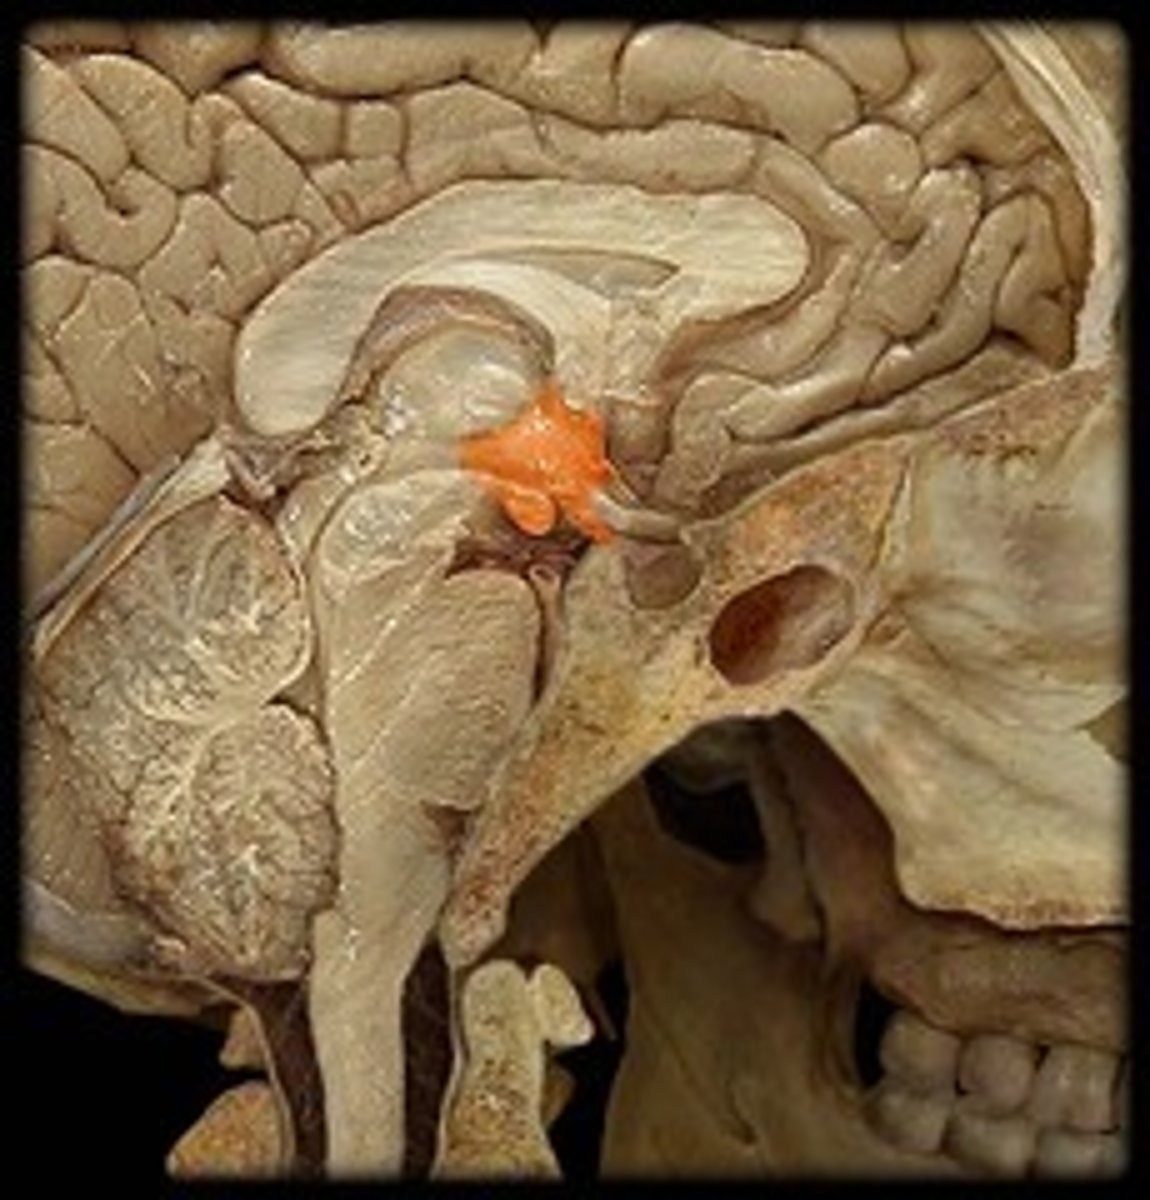

Pituitary gland

Acidophils Cells of the anterior Pituitary Gland

Secrete growth hormone, prolactin

Basophils cells of the anterior pituitary gland

Secrete FSH LH and TSH

Pituicyte cells of the posterior pituitary gland